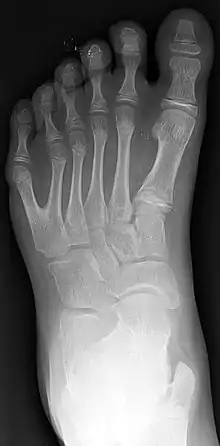

Полідактилія — Рентгенівський знімок 10-річного хлопчика